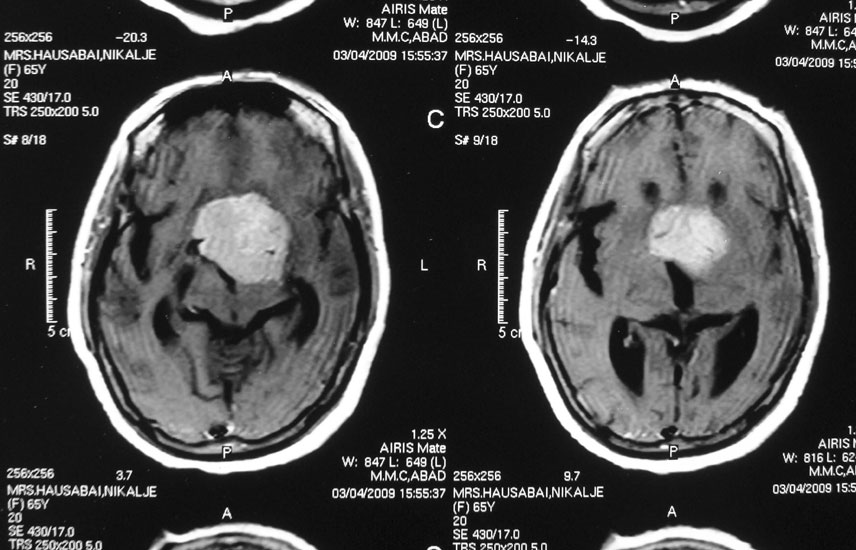

Intraventricular Meningiomas

Meningiomas that occur within the ventricular cavities of the brain constitute a special group, and need special surgical planning to safeguard the vital areas of the brain.